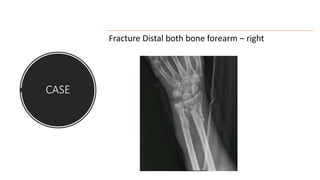

CASE

Secondary survery

Clinically right upperlimb # - wrist

Fracture Distal both bone forearm – right